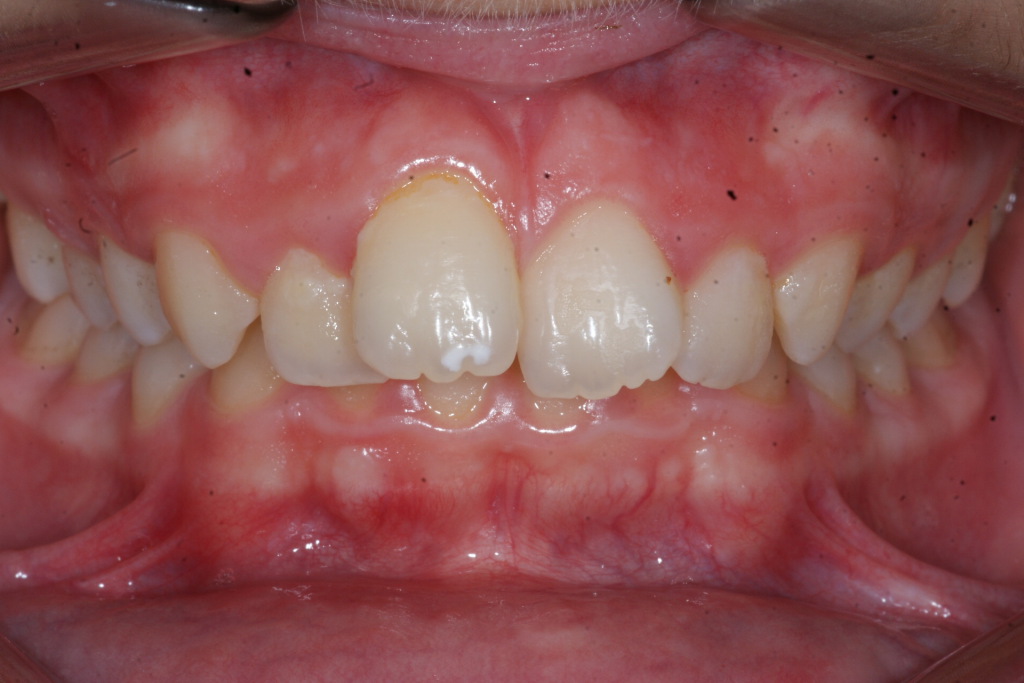

Correction d’une malocclusion de type Classe II.  Des appareils fixes (boîtiers) et une expansion palatine furent nécessaires pour améliorer ce sourire.  Traitement chez un adolescent, réalisé en 21 mois.